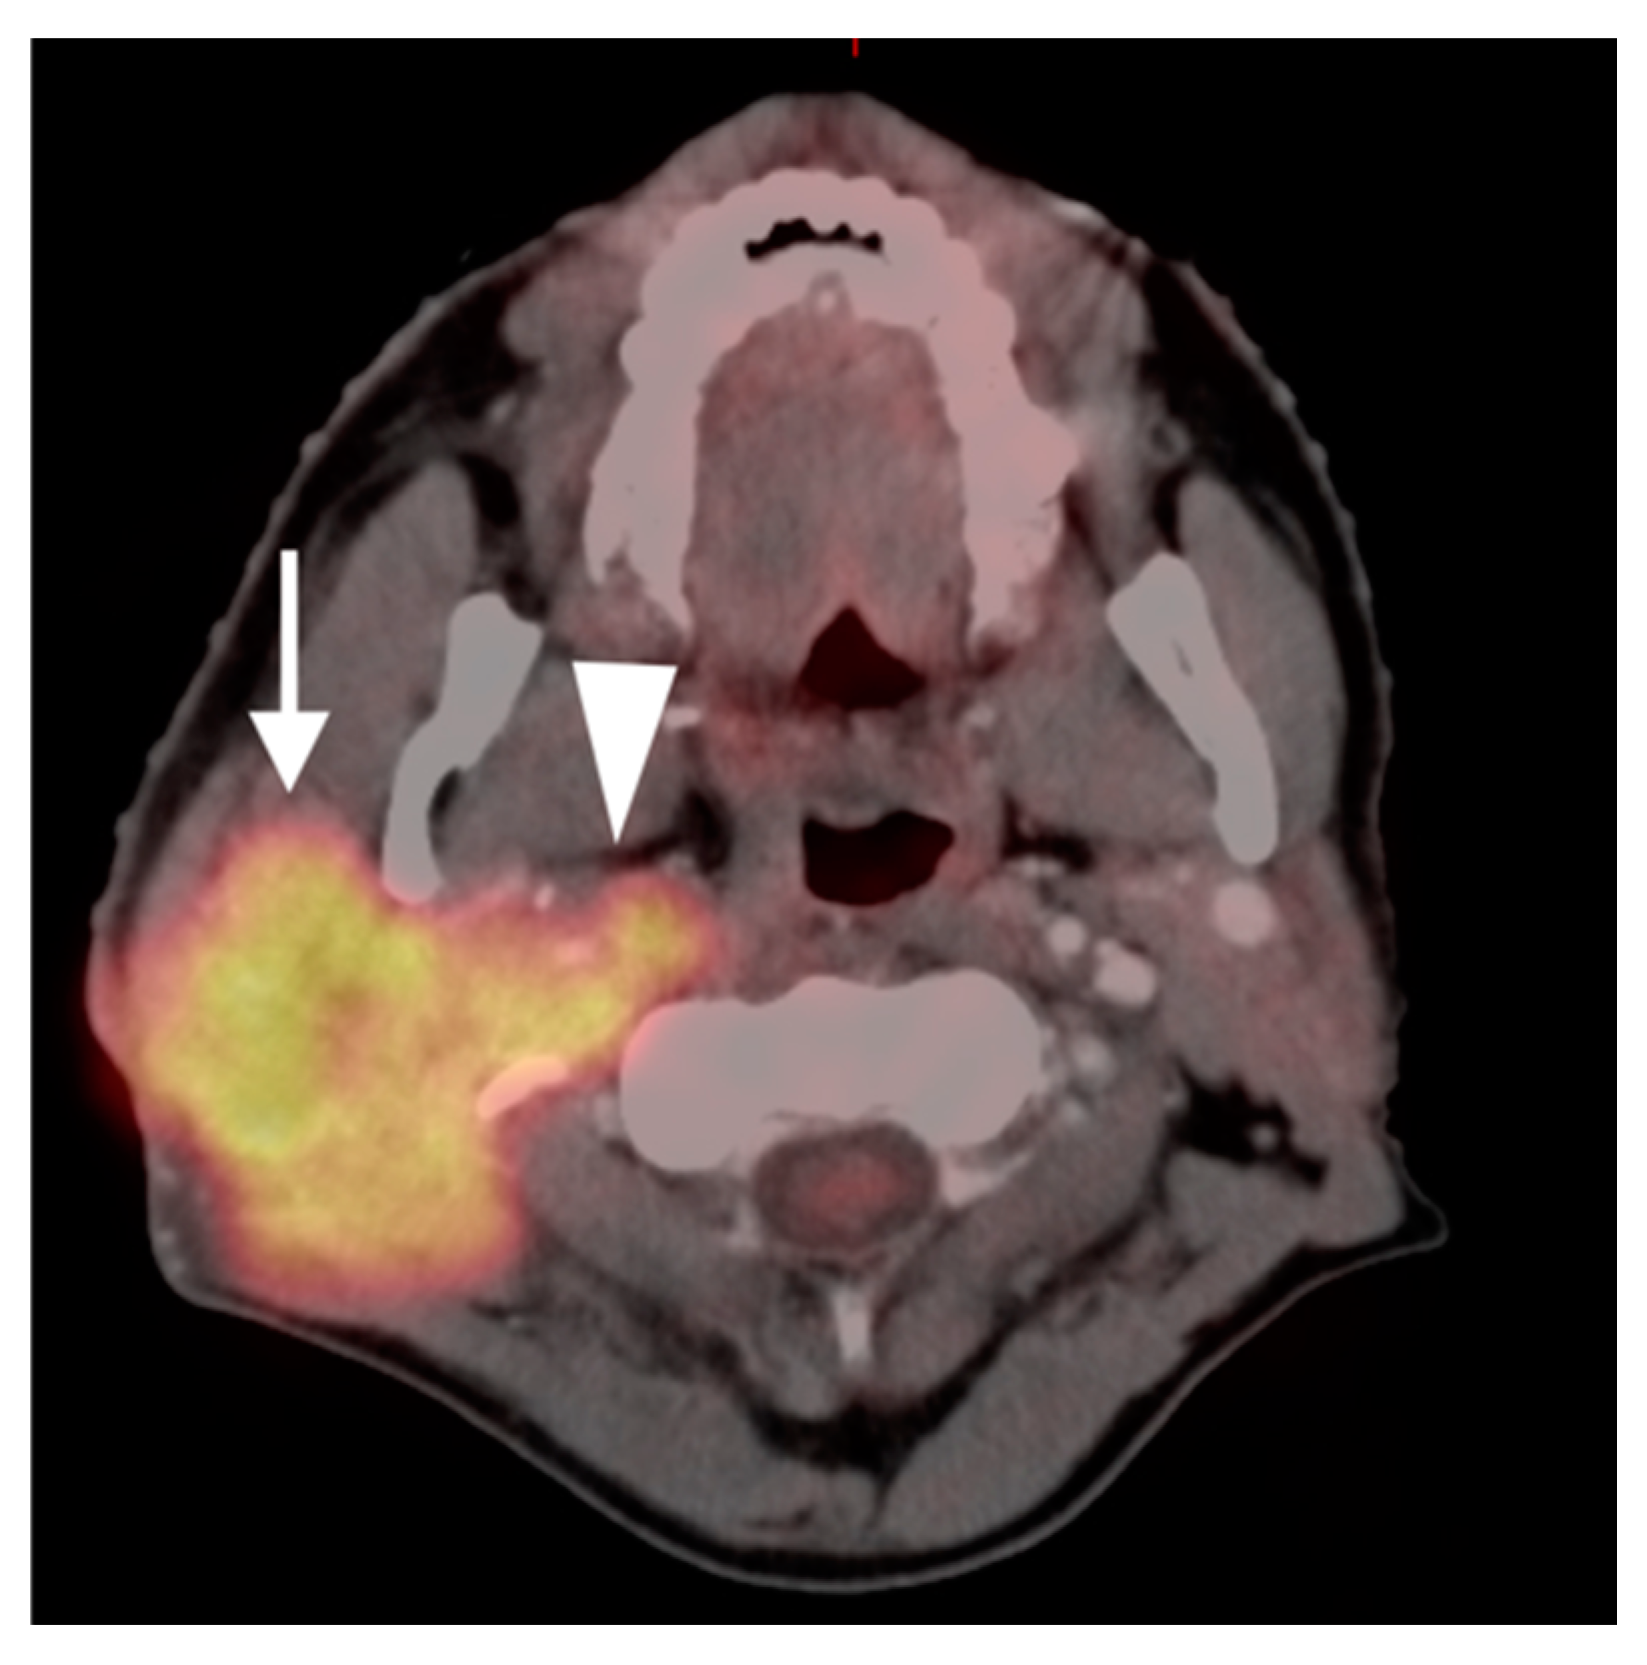

2.5. Major and Minor Salivary Gland, Lacrimal Gland Tumors

- Warthin tumor